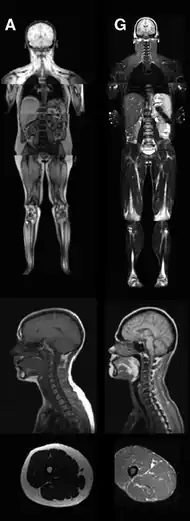

| An MRI image illustrating the lack of subcutaneous fat of a patient with the disease (G) compared to a control patient (A) | |